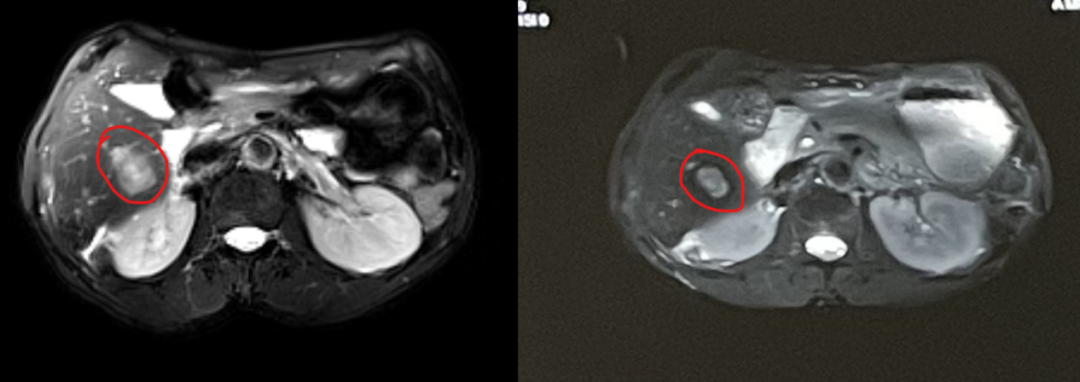

After exhausting conventional options, the family learned about heavy ion therapy’s efficacy in pancreatic cancer through patient communities. They consulted Dr. Chen Weizuo of Wuwei Heavy Ion Center (home to China’s first domestically developed heavy ion therapy system). Following a multidisciplinary expert panel review, Deputy Director Zhang Yanshan explained: "While Mr. Pu has developed resistance to first-line therapies, his high CPS expression suggests carbon ion therapy could enhance local tumor control and reshape the immune microenvironment, potentially re-sensitizing him to immunotherapy." Mr. Pu’s family chose to pursue treatment despite challenges. Over 15 sessions (60 Gy (RBE)/15 fractions for the liver, 58.5 Gy (RBE)/14 fractions for the pancreas), he experienced minimal side effects. Post-treatment, his CA19-9 dropped to 9,450 U/ml. A follow-up in February 2025 revealed further decline to 1,975 U/ml, with significant tumor shrinkage. Encouragingly, he qualified for a clinical trial targeting the KRAS G12D mutation, reigniting his fight.

(Imaging shown: Tumor regression post-carbon ion radiotherapy, left pre-treatment, right 1-month post-treatment.)